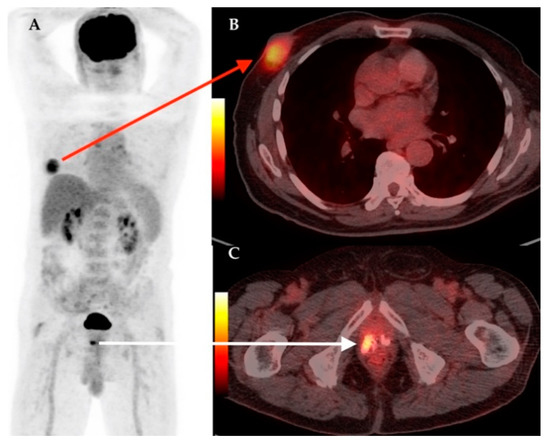

| 17 | 61 | IDC | RM + ALND | Yes | Yes | IIIB | LN | LN, Lu, M, Bn | 3.1 | Hodgkin Lymphoma | 11.6 |

| 21 | 61 | IDC | RM + ALND | Yes | Yes | IIC | LN | – | 2.38 | Thyroid cancer | 23.1 |